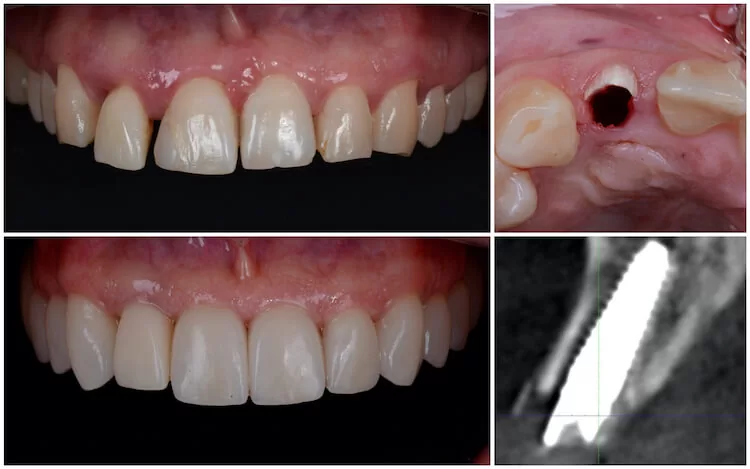

Fogimplantátum Budapest – tartós, esztétikus megoldás a SmileCenter Fogászatnál

Egy hiányzó fog nemcsak esztétikai problémát jelenthet, hanem az étkezést, a beszédet és az önbizalmat is befolyásolhatja. A SmileCenter Fogászat Budapesten olyan fogimplantátum megoldásokat kínál, amelyekkel újra természetesen mosolyoghat, magabiztosan étkezhet és kényelmesen élhet – mintha csak a saját fogait kapná vissza.

A beavatkozás minden esetben alapos tervezéssel kezdődik. Az implantációt a legmodernebb digitális technológiával és 3D tervezéssel végezzük, így a folyamat biztonságos és pontos.

Részletes vizsgálat, panorámaröntgen és 3D CT alapján meghatározzuk, hogy alkalmas-e a csont az implantátum beültetésére.

Digitálisan megtervezzük az implantátum helyét, méretét és dőlését, hogy a végeredmény funkcionálisan és esztétikailag is tökéletes legyen.

A beavatkozás helyi érzéstelenítésben történik, teljesen fájdalommentesen. A műgyökér beültetése után 2–3 hónapos gyógyulási idő következik, amíg a csont rögzíti az implantátumot.

A csontosodás után elkészítjük a végleges koronát vagy hidat, amely színében és formájában is illeszkedik a természetes fogakhoz.